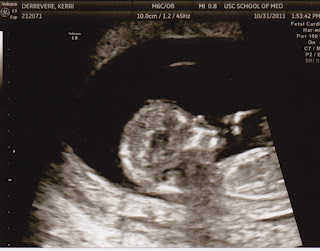

We had another appointment today with Dr. Browne. It went very well and he had many good things to say about you. He showed us that your tummy and bowel were in the same place and not much has changed. You are growing well and are already 1lb 15oz inside my belly. We took a video of you but you were being stubborn and kept your little foot in your mouth the whole time. I am so excited about getting to meet you but you better behave and stay in for a while until you are big enough to fight! I love your kicks. Your mommy had about a million questions for Dr. Browne and he answered every one and made me feel much better that you would be a strong little angel and had an excellent chance to make it. Your dad and I are still trying to decide where to have you but we have a few months to get that all figured out. In the mean time I have already started setting up your nursery and keep imagining what it will be like to hold you in my arms and rock you to sleep. The other big news I'm sure everyone was wondering is what we have decided to name you! And we have chosen Owen. It had to be short considering your last name is so long! I love you so much and so does your daddy! Here is your first video before you were born.